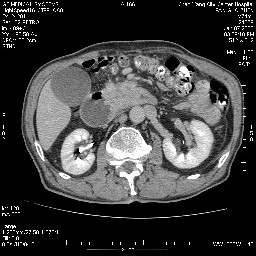

女,74岁,呕吐10余日

十二指肠水平段腔内占位伴梗阻,中等度较为均匀的强化,洗脱慢,区域淋巴结显示增多,符合腺癌表现。下腔静脉变异。

十二指肠降段扩张,水平段狭窄成鼠尾状,肠壁明显增厚,胰腺勾突增大成不均匀强化,其内可见低密度区,胆囊增大,1十二指肠水平段腺癌侵犯胰腺勾突可能大,2胰腺癌侵犯十二指肠(只有胆囊增大没有肝内外胆管扩张不好解释)代除外.

上消化道造影见十二指肠结节状充盈缺损,ct增强十二指肠壁局限性增厚并强化,考虑十二指肠壶腹癌?

十二指肠降段扩张,水平段狭窄成鼠尾状,肠壁明显增厚,胰腺勾突增大成不均匀强化,其内可见低密度区,胆囊增大,1十二指肠水平段腺癌侵犯胰腺勾突可能大,2胰腺癌侵犯十二指肠 。

今日手术结果:胰腺钩突癌侵犯十二直肠,腹腔淋巴结转移.